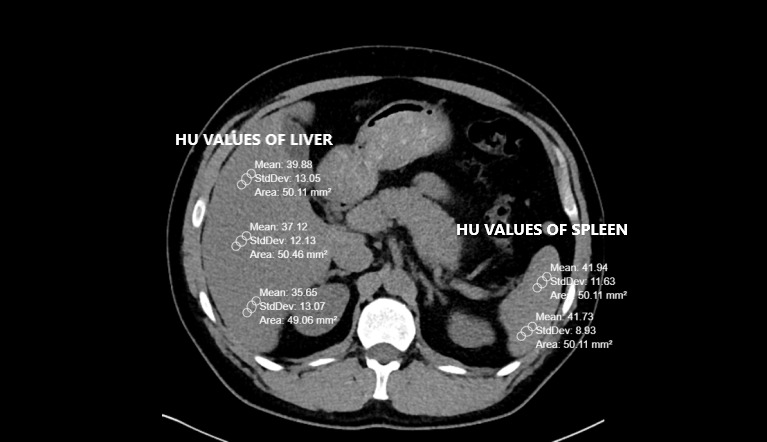

Pre-existing CT scans had been performed with a 256-slice multi-detector CT scanner (Somatom, Siemens Healthcare, Erlangen, Germany). Abdominal CT images were reconstructed by the authors on coronal, axial and sagittal planes. All CTs were taken without contrast and in a supine position. The other CT scan parameters were as follows: rotation time, 0.35s; thickness, 1mm; FOV (field of view), 30-40 cm.8,9 Liver and spleen HU values were calculated from a minimum of three different points. The presence of a HU difference <10 between the liver and spleen is one of the two FLD criteria used in the study.3 Therefore, it was important to obtain spleen values along with the liver. Region of interest (ROI) was selected as approximately 50 units. Liver CT window (width (W):150 Hounsfield units (HU), length (L):30 HU) was used during the measurements (Figures 1 and 2).

The livers and spleens of sample patients were also evaluated in the abdominal window (W:400 HU L:50 HU). The measurement points were chosen from different liver segments. Measurements were not taken from regions where focal fat deposition was observed (e.g., periportal areas and around the gallbladder). Peripheral area measurements were preferred because of hilar vascularity, when measuring spleen HU.